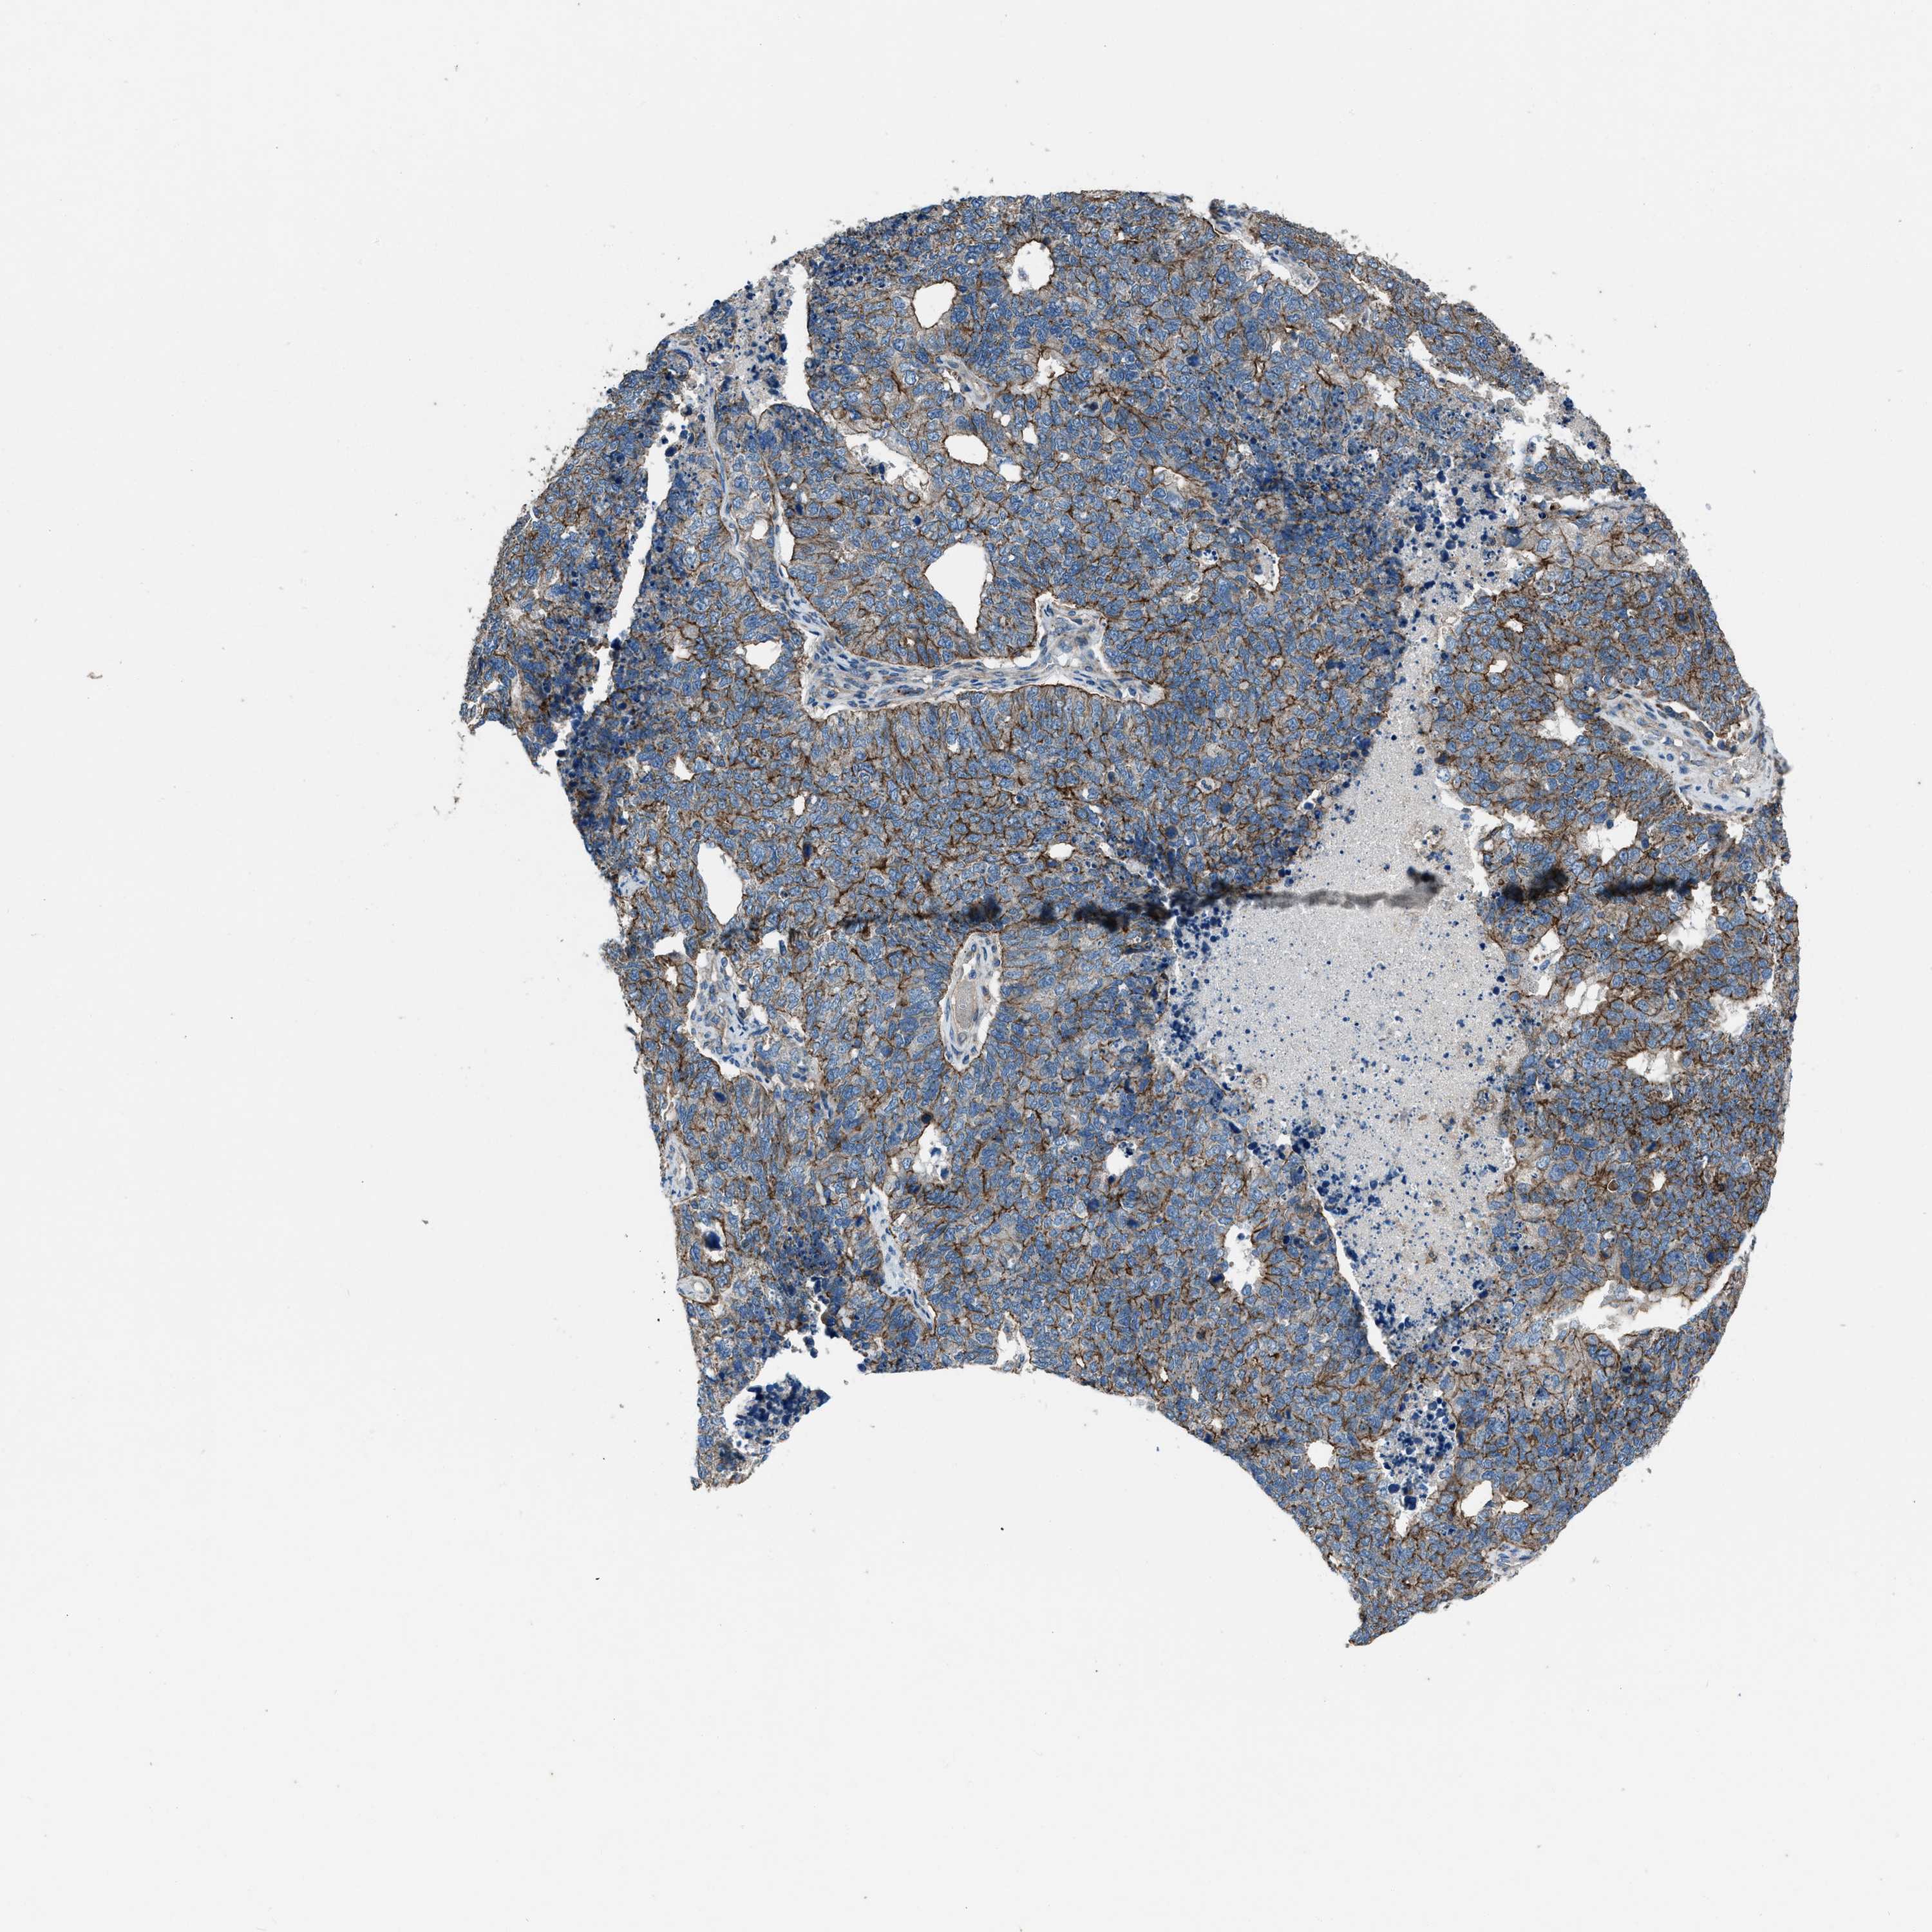

CERVICAL CANCER - Protein expressioni

A mouse-over function shows sample information and annotation data. Click on an image to view it in a full screen mode. Samples can be filtered based on level of antibody staining by selecting one or several of the following categories: high, medium, low and not detected. The assay and annotation is described here.

Note that samples used for immunohistochemistry by the Human Protein Atlas do not correspond to samples in the TCGA dataset.

Antibody stainingi

Antibody staining in the annotated cell types in the current human tissue is reported as not detected, low, medium, or high, based on conventional immunohistochemistry profiling in selected tissues. This score is based on the combination of the staining intensity and fraction of stained cells.

Each image is clickable and will lead to virtual microscopy that enables deeper exploration of all samples and also displays staining intensity scores, fraction scores and subcellular localization as well as patient and tissue information for each sample.

Antibody HPA020095

Antibody HPA020138

Antibody CAB010878

Antibody CAB080402

Squamous cell carcinoma, NOS

Adenocarcinoma, NOS